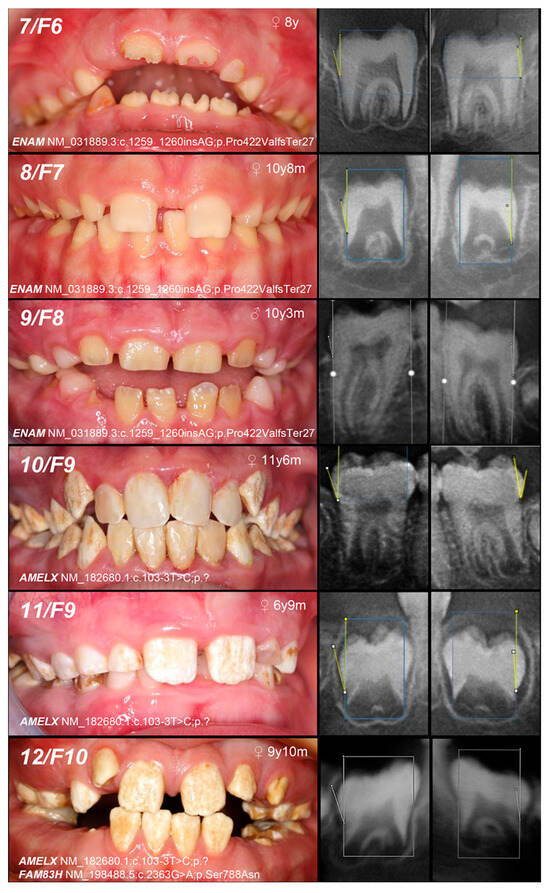

| Patient (n) Family (n) | Phenotype | OMIM, Mode of Inheritance, Gene Affected | Gene Variant | Zyg. | Protein Outcome | References | Fam. Segreg. | ACMG |

|---|---|---|---|---|---|---|---|---|

| 1, F1 | Hypoplastic (localized) | IB, AD, ENAM | c.92T>C | +/− | p.Leu31Pro | novel | Mo (AC) Fa (U) | likely pathogenic (PP1:moderate, PM5:moderate, PM2:moderate) |

| 2, F2 | c.306G>A | +/− | p.Trp102Ter | novel | Mo (AC) FaS (U) | likely pathogenic (PVS1:very strong, PM2:moderate) * | ||

| 3, F3 | Hypoplastic (generalized) | c.588+1del | +/− | p.? | [25] | Mo (U) Fa (AC) | pathogenic (PS4:strong, PVS1:strong, PM2:moderate) | |

| 4, F4 | Hypomineralized (hypoplastic) | IB, AD, ENAM | c.1259_1260insAG | +/− | p.Pro422Val fsTer27 | [5] | Mo (AC) FaS (U) | pathogenic (PS4:strong, PVS1:strong, PM2:moderate) GnomAD: 0.0002517 |

| 5, 6, F5 | Hypoplastic (generalized—recessive trait; localized, pitting, grooving—dominant trait) | IC, AR/AD, ENAM | −/− | [25] | MoFa (UC) | |||

| 7, F6 | MoFaS (UC) | |||||||

| 8, F7 | MoFa (UC) | |||||||

| 9, F8 | MoFa (UC) | |||||||

| 10, 11, F9 | Hypomineralized (heterogeneity) | IE, XLD, AMELX | c.103-3T>C | +/− | p.? | [26] | Mo(U) Fa (AC) | likely pathogenic (PP1:strong, PM2:moderate)* |

| 12, F10 | +/− | Mo (AC) Fa (NA) | ||||||

| and IIIA, AD, FAM83H | c.2363G>A | +/− | p.Ser788Asn | [26] | benign (BA1:stand-alone, BS2:strong, BP4:supporting, BP6:strong) | |||

| 13, F11 | Hypoplastic (heterogeneity) | IE, XLD, AMELX | c.485delT | 0/− | p.Phe162SerfsTer13 | novel | MoS (A) Fa (NA) | likely pathogenic (PVS1:very strong, PM2:moderate) |

| 14, F12 | Hypomineralized (pigmented hypomature) | IIA2, AR, MMP20 | c.389C>T | −/− | p.Thr130Ile | [27] | MoFa (UC) | likely pathogenic (PP5: strong, PM2: moderate) GnomAD: 0.001747 |

| 15, F13 | +/− | Mo (U) Fa (NA) | ||||||

| and c.446G>A | +/− | and p.Trp149Ter | novel | likely pathogenic (PVS1:very strong, PM2:moderate) GnomAD: 0.00000398 |